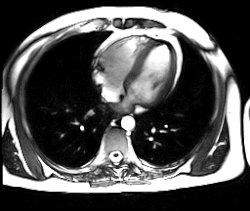

Magnetická rezonance (též MR, MRI, z anglického „magnetic resonance imaging“) je zobrazovací technika používaná především ve zdravotnictví k zobrazení vnitřních orgánů lidského těla. Pomocí MRI je možné získat řezy určité oblasti těla, ty dále zpracovávat a spojovat až třeba k výslednému 3D obrazu požadovaného orgánu. Magnetická rezonance využívá silné statické magnetické pole (řádově jednotky T) a elektromagnetické vlnění (s frekvencemi v řádu desítek až stovek MHz). Na rozdíl od CT vyšetření, které je s MR někdy alternativní, nenese žádná rizika způsobená ionizačním zářením (nulová radiační zátěž). Nevýhodou vyšetření MR je určitá hlučnost zařízení. Podstatou odlišení jednotlivých tkání a patologií je jejich rozdílné chování při stejném vnějším působení. Vyšetření se provádí bez kontrastní látky nebo s ní (např. gadolinium vpichem do žíly).

Použitím gradientních magnetických polí v přesně specifikovaných okamžicích vyšetření se v různých místech sledované oblasti těla dočasně a řízeně změní velikost magnetického pole a tím i rezonanční frekvence jader. Změřené frekvence indukovaného napětí se výpočtem převedou na polohu v obraze a amplituda napětí se zobrazí na škále šedé. Různé úrovně šedé potom svědčí o různých vlastnostech měřených tkání. K interpretaci obrazů používá zejména sledování rozhraní, na kterých se mění intenzita signálu.